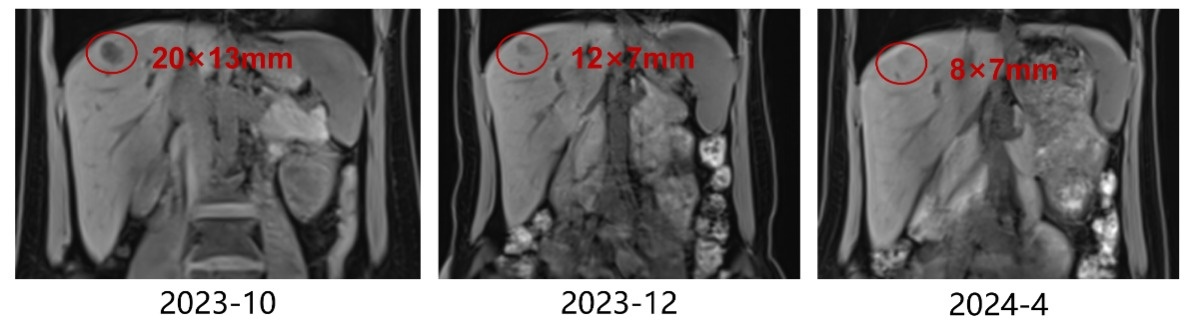

上腹部MR:肝脏多发占位(最大者位于S7,大小约20mm×13mm),考虑转移瘤可能性大。

疗效评估:右乳肿物均较前明显缩小,肝脏多发转移瘤较前缩小;部分缓解(PR)

疗效评估:疾病进展(PD),PFS仅2个月,考虑原发性内分泌治疗耐药。

上腹部MR(2024-9)肝脏多发转移瘤,数量较前增多,S2、S4、S5部分结节较前增大,S4包膜下结节较前稍缩小,S6结节同前相仿。

疗效评价:肝脏病灶明显缩小,最佳疗效PR,PFS>11个月。

肝脏转移瘤(较大者)缩小情况

0926-04.png